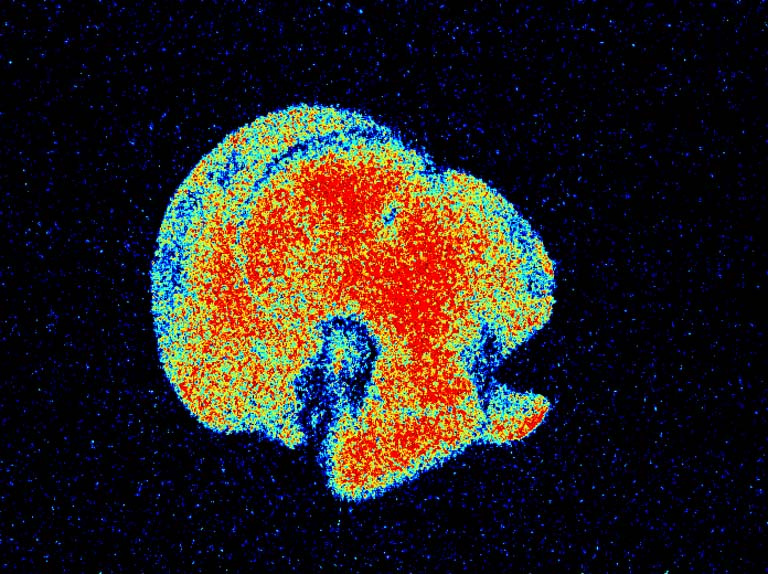

This is an image showing the presence and concentration of carbon nanotubes in a mouse’s liver. By taking this image, as well as many other images of livers at different time points after the injection, we were able to see how long it takes the carbon nanotubes to get to the liver and how long they stay in the tissue.